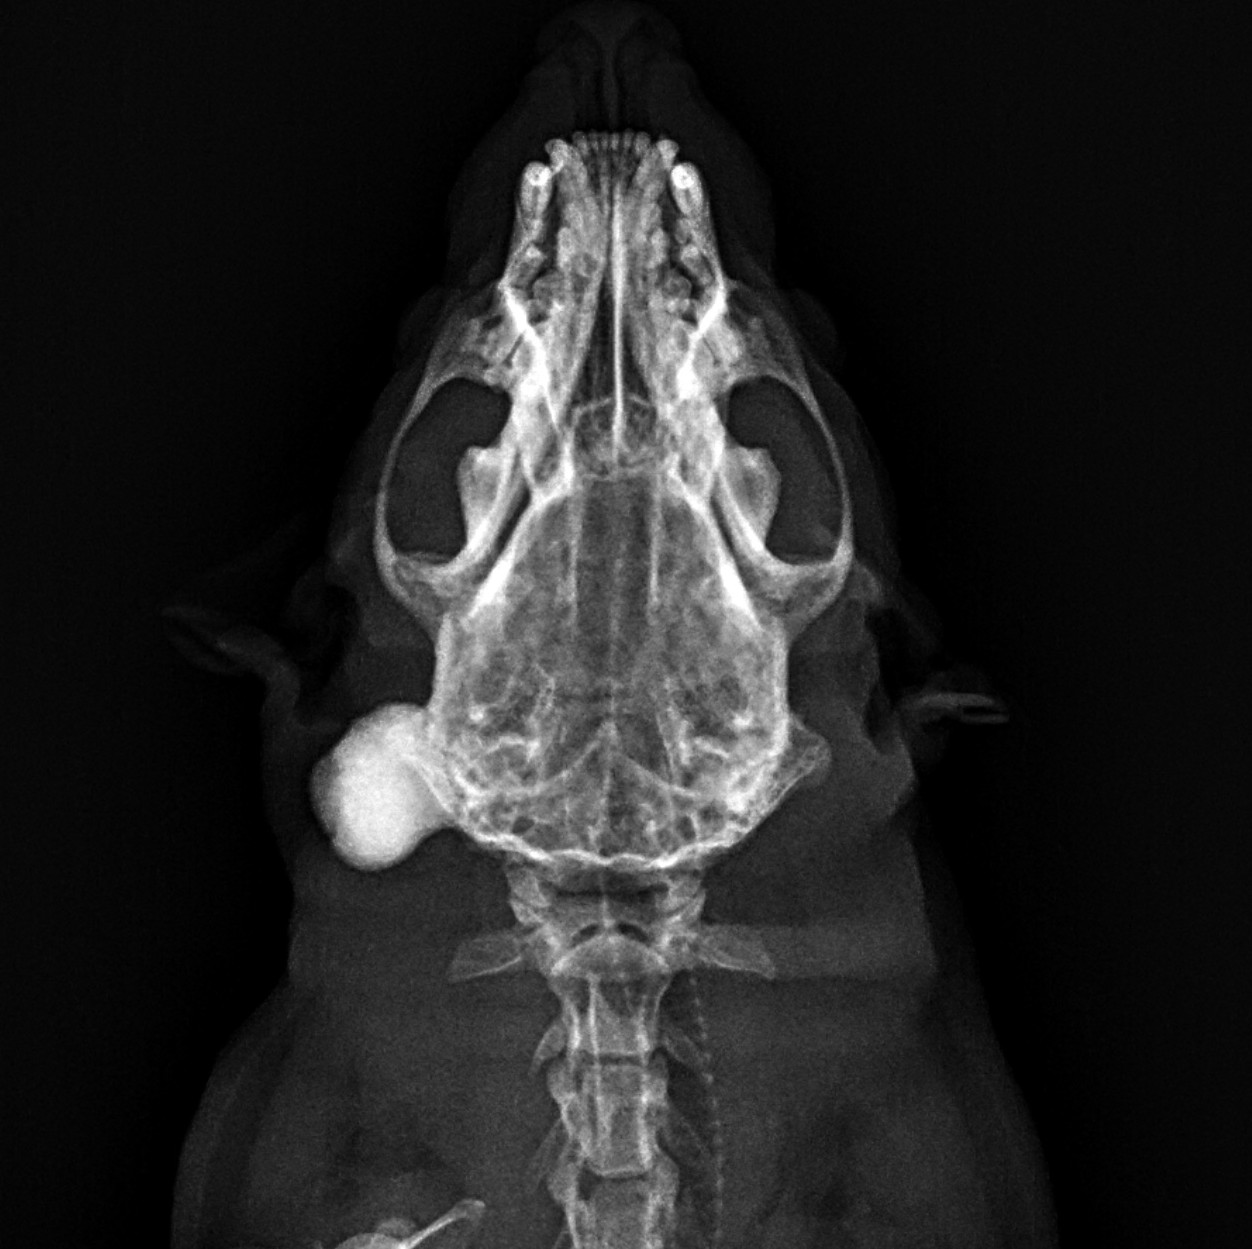

頭部のしこりを主訴に来院され、触診にて右後頭部に1cm大の硬性腫瘤を認めました。X線検査にても頭蓋骨と連続性のある不透過性の画像が得られております。

1ヵ月程度抗生剤や消炎剤等で経過を追っていましたが、増大傾向を示したため術前検査を実施後、第53病日にCT検査及び切除生検を行いました。

手術前には1.6㎝程度に増大していました。皮膚を切皮後、鈍性剥離にて腫瘤部を露出し、頭蓋骨への影響を最小限にする位置での切除のため、CTで確認した切除ラインを骨鋸(サジタルソー)により切除しました。